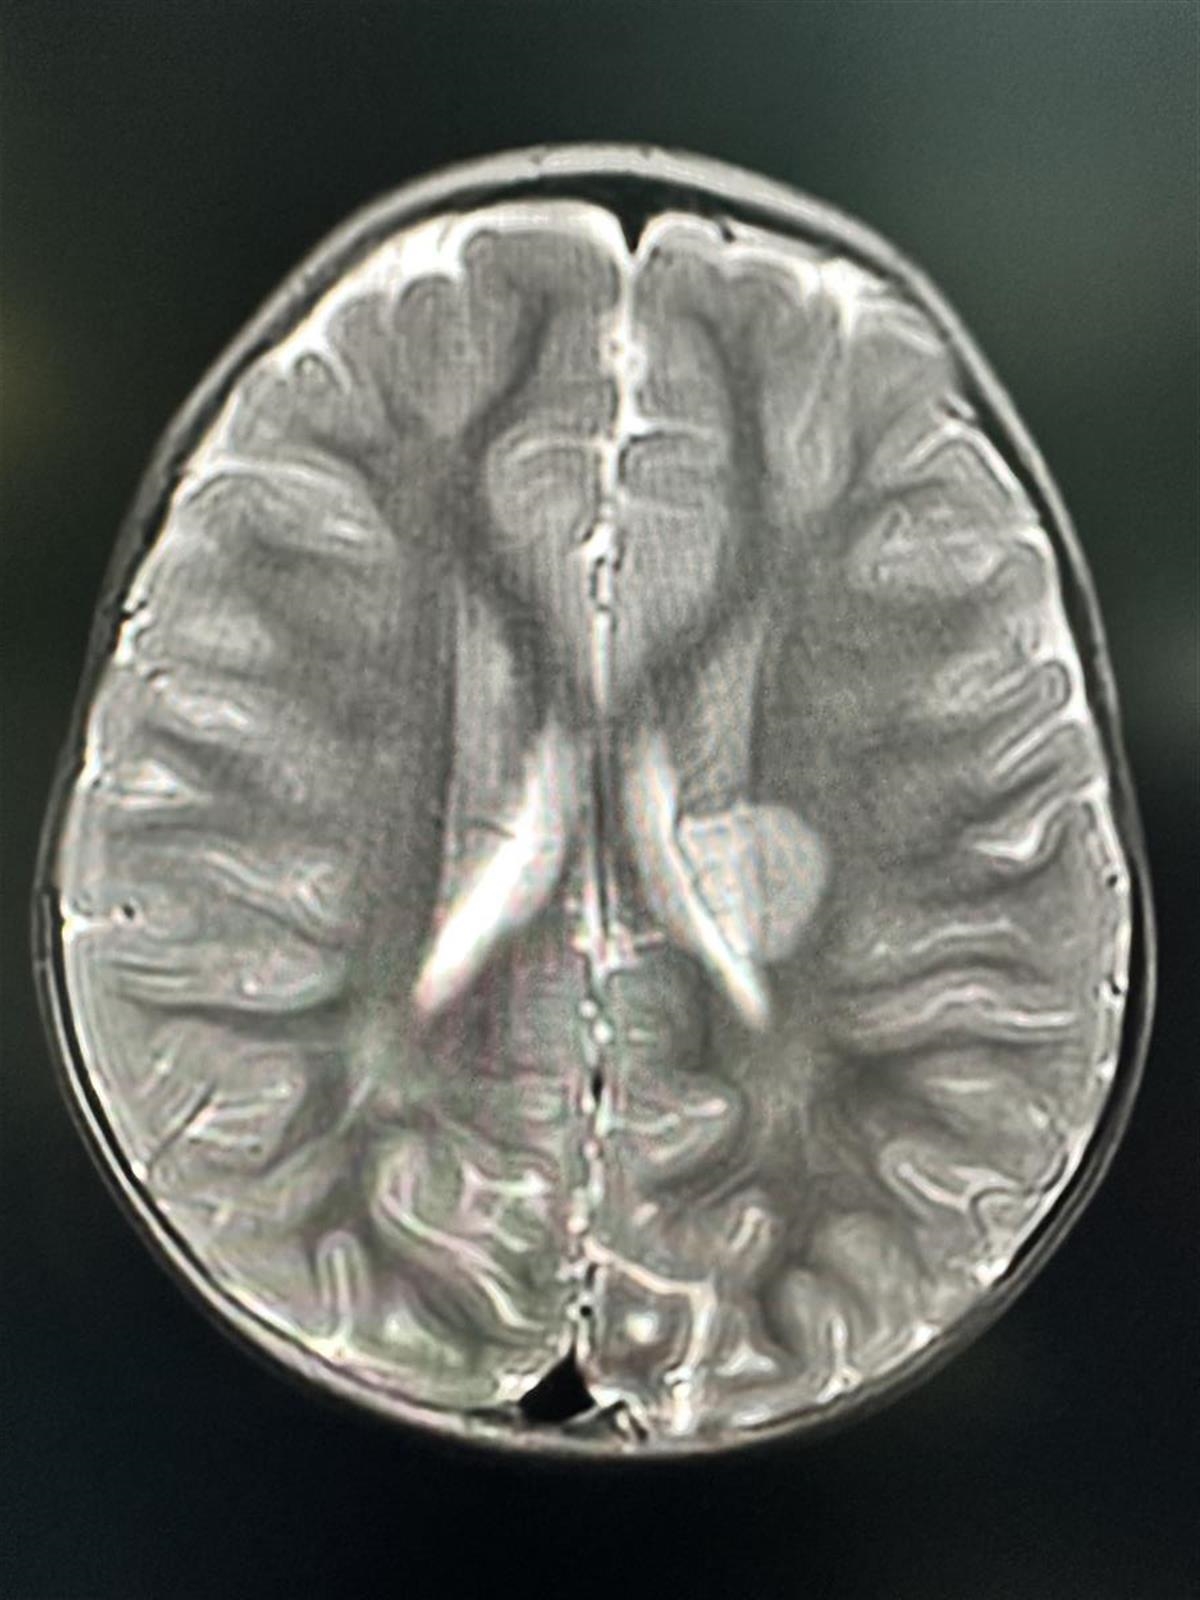

見此情況,家長急忙將他送到當地醫院就診,醫生檢查發現,言言右下肢和右上肢肌力很差,完全不能活動,且伴有語言減少。根據磁振造影檢查結果,醫師懷疑言言腦部有梗塞,可能是中風了,隨即請家長把言言轉到大醫院,於是家長便帶著言言到武漢兒童醫院。

武漢兒童醫院的醫生為言言細心診斷,發現他是急性腦梗塞—缺血性腦血管病,也就是大腦血管出現梗阻,導致腦部缺血,必須動手術。醫生劉新獻說:「腦部梗塞缺血須盡快想辦法疏通阻塞的血管,一旦錯失時機,腦組織將很難恢復,可能留下偏癱等後遺症。」